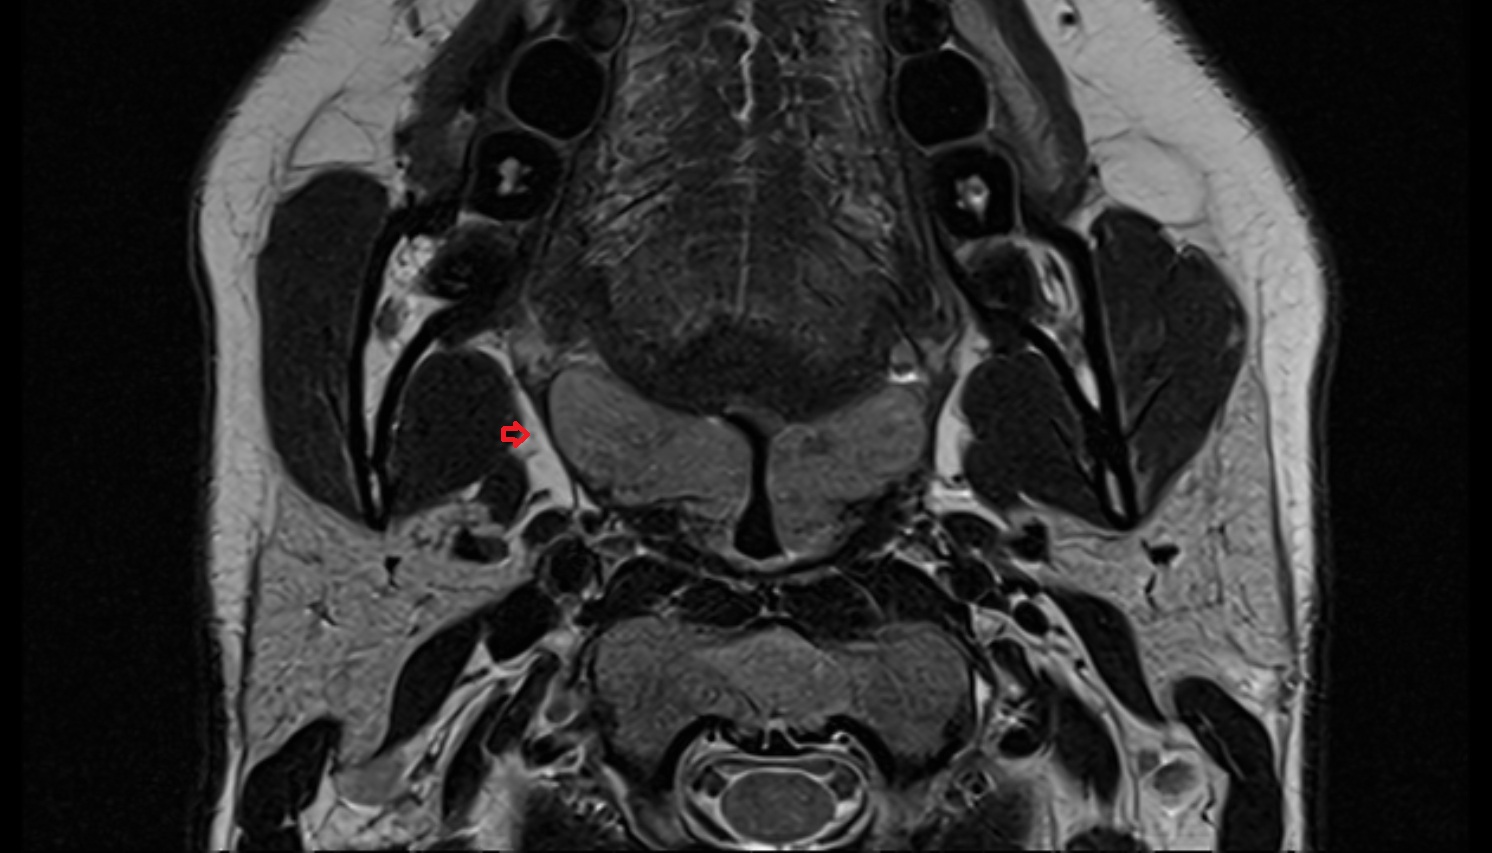

- Seminal vesicle

- Peripheral zone of prostate

- Anterior Fibromuscular Stroma of prostate

- Central zone of prostate

- Transitional zone of prostate